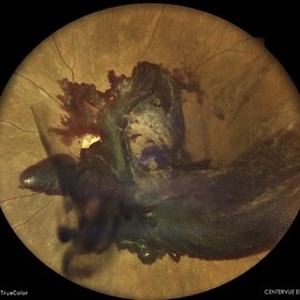

Retinoblastoma

Wide-field color fundus photograph of a 2-month old female with retinoblastoma.

Photographer: Dr. Akansha Sharma-Retina Foundation, Ahmedabad

Condition/keywords: RB gene mutation, retinoblastoma